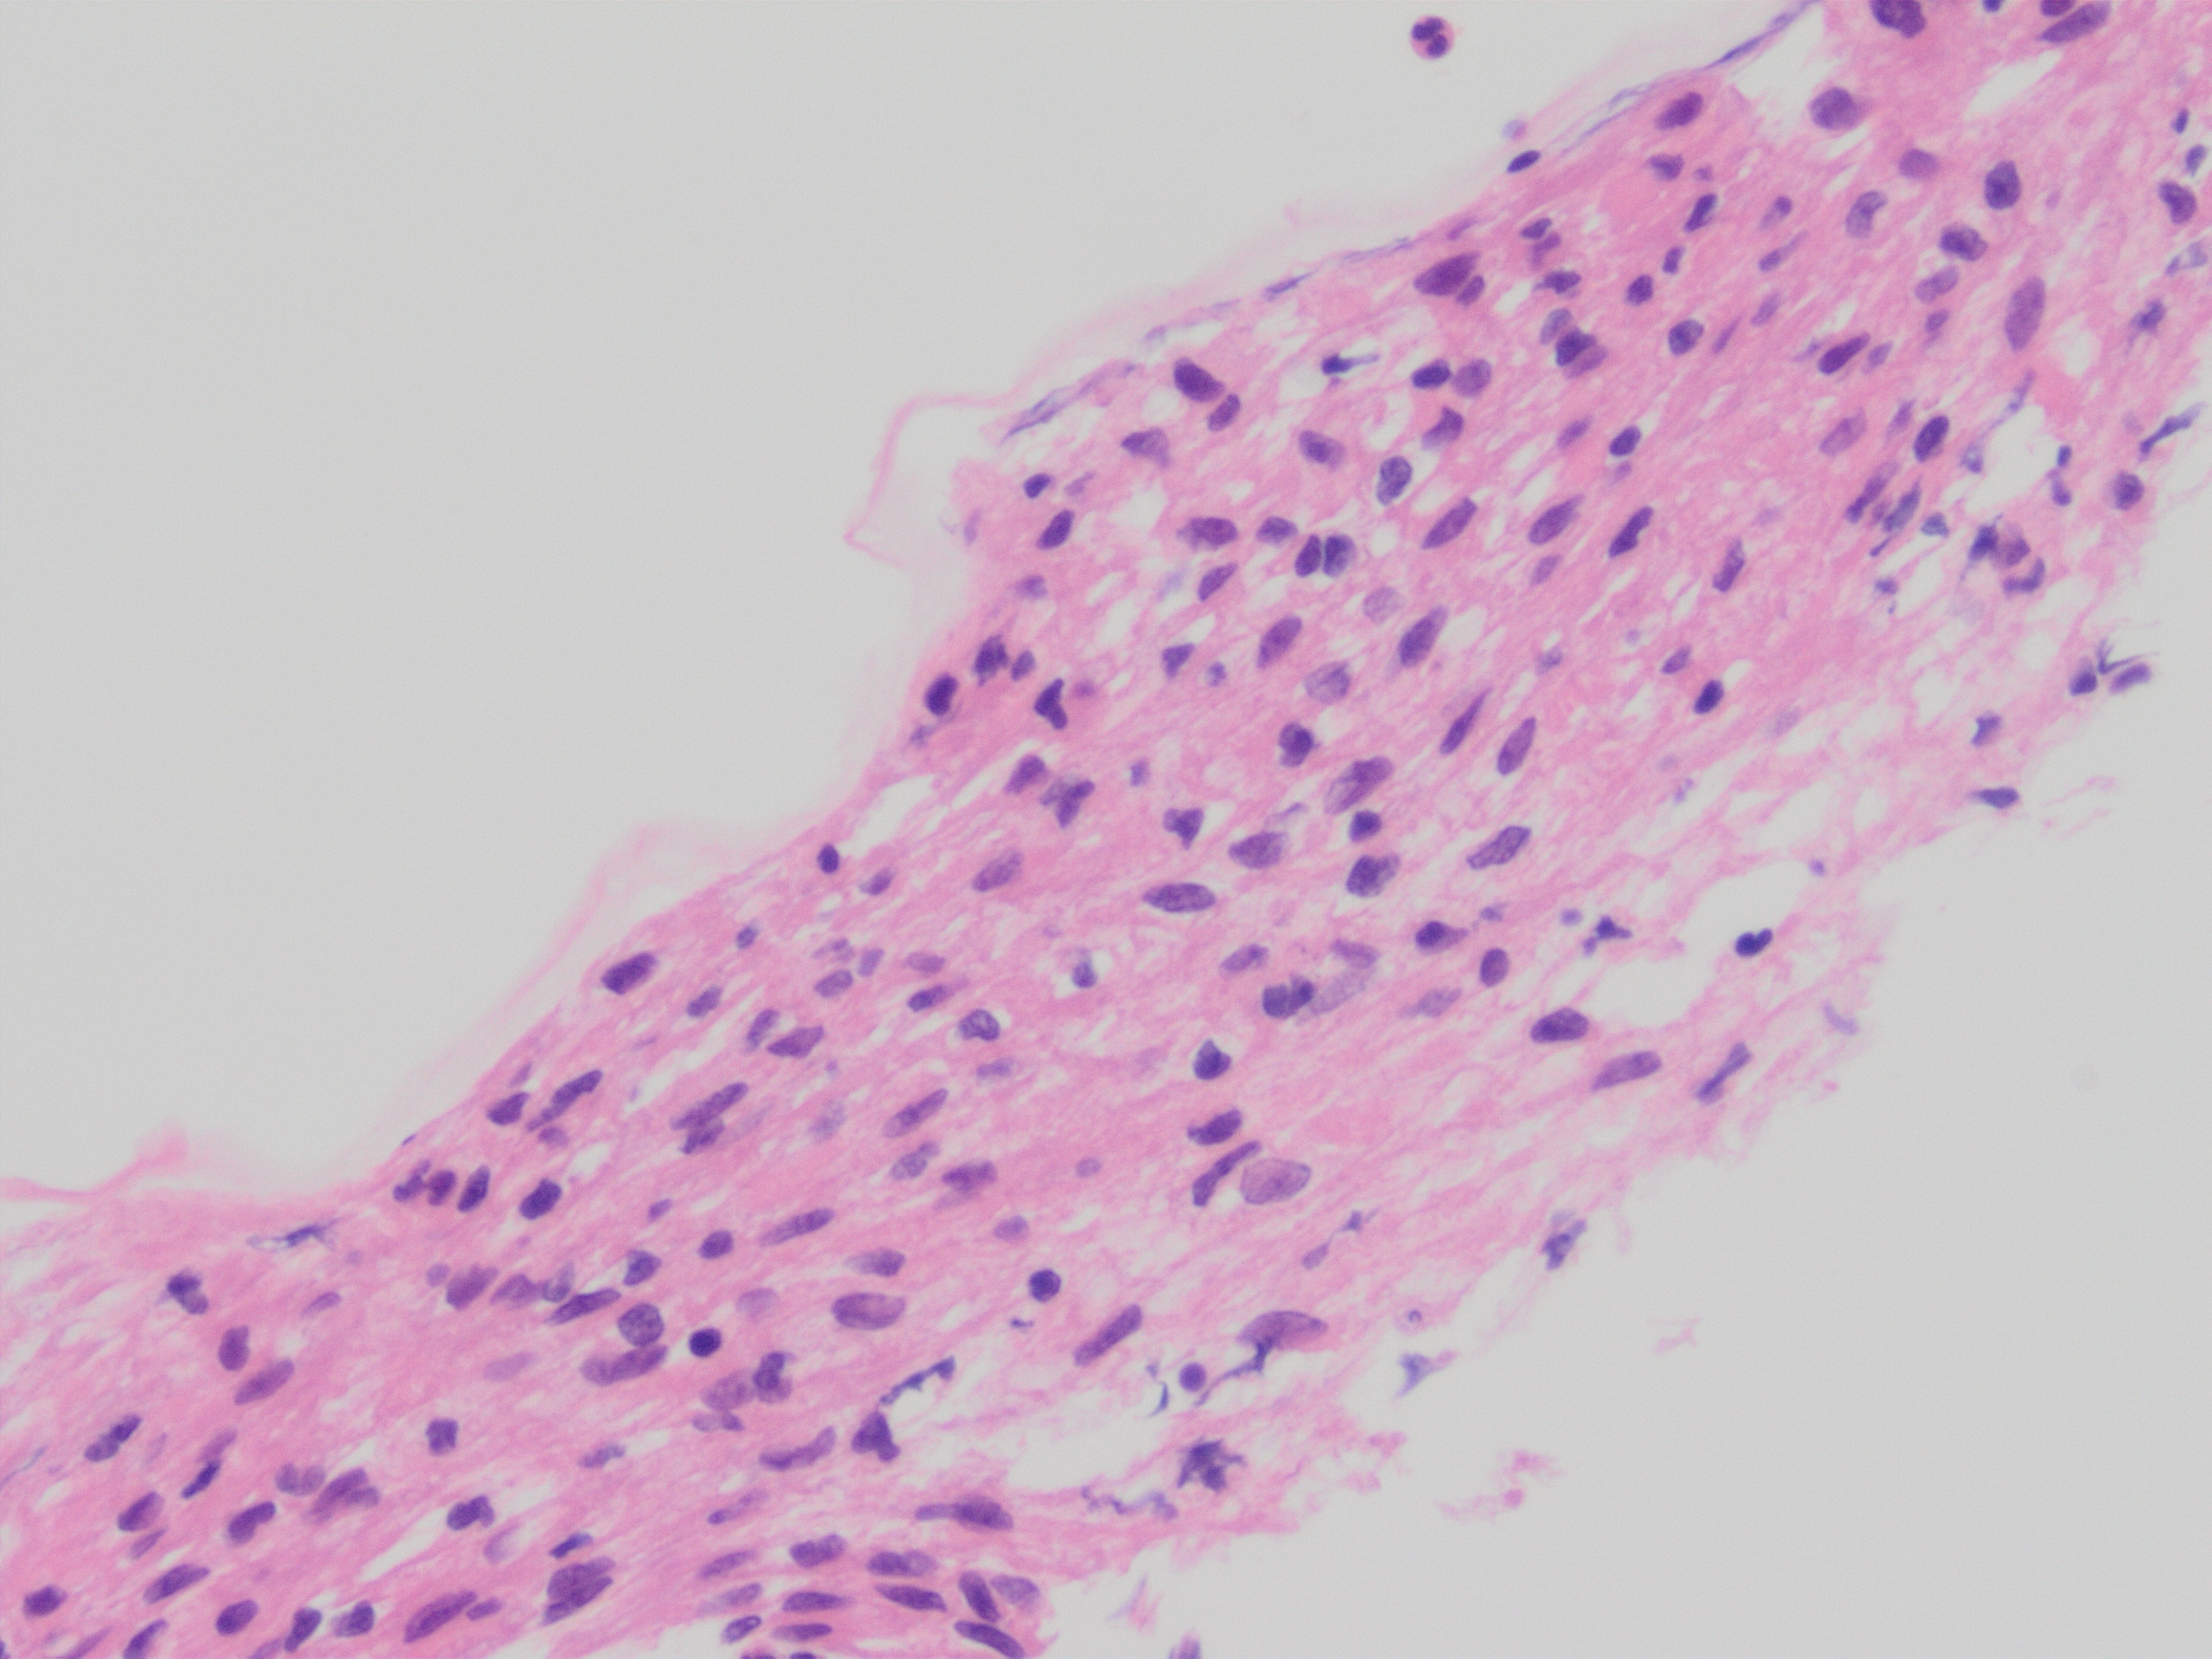

Immunohistochemistry was diffusely positive for Sox-10 and negative for C117 (C-kit), DOG1, SMA, CD34, supporting neural crest origin. On cytology, note a large tissue fragment with variable cellularity showing oval to wavy, “fishhook” nuclei on higher magnification and indistinct cell borders. On cell block, note the abundant filamentous cytoplasm and subtle nuclear palisading.